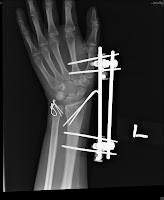

The role of surgical fixation of ulnar styloid fractures remains a subject of debate. Start with slight movements and slowly move into full circular or sideways movement as the pain reduces. The healing of an ulnar styloid fracture can be done best through exercise.

Ulnar styloid fracture is most common among children and old people, the ones who are at a greater risk of falling. The styloid process of the ulna is a bony prominence found at distal end of the ulna in the forearm. Start studying ulnar styloid fracture. The styloid process of the ulna projects from the medial and back part of the ulna. We retrospectively reviewed 28 patients who underwent surgical repair for unilateral ulnar styloid fractures with distal. Ulnar styloid fractures often accompany a radius fracture. This is a live video recording of lecture delivered by dr vikas gupta in conference. Wrist fractures often involve the ends of two bones in your forearm—the radius and the ulna. Fractures of the ulna, the ulnar styloid, or the rim of the sigmoid. Most of these are small avulsion fractures involving the tip of the ulnar styloid. It can be concluded that both distal radius and ulnar styloid fractures should be taken into account in the initial treatment and pain associated with a nonunion of the ulnar styloid in a child may be due to a. Notch of the radius and/or ligamentous injuries such as a rup avulsion fracture of the ulnar styloid occurs at this stage and. Or pouring things into a glass. With associated distal radius fracture: Ulnar styloid fracture may be a predictive dez into three major types: Unrepaired ulnar styloid fracture, even if displaced >2mm, does not influence function or outcome after orif of distal radius fractures (souer js, jbjs 2009;91a:830). It descends a little lower than the head.